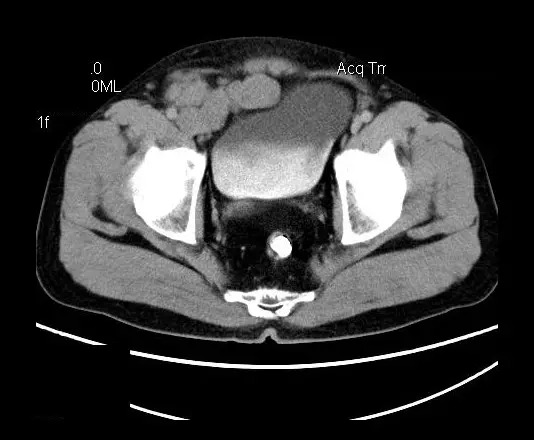

男,50岁,发现盆腔包块一月,无明显触痛,不伴发热。

【影像表现】

盆腔右前侧及邻近腹股沟区可见多发大小不等的聚集生长的结节影,病灶呈软组织密度,边缘尚规整,分界尚清,增强扫描可见不均匀强化。膀胱局部受压,盆腔未见明显肿大淋巴结影。

“盆腔”多发性神经鞘瘤

增强影像表现:神经鞘膜肿瘤增强后,由于Antoni A区与B区以不同比例混合而强化不一,呈不均匀斑片状,条状强化。Antoni A 区富血供,中等或明显强化,Antoni B区乏血供,强化多不明显。